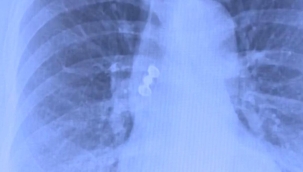

Beyin ve omuriliği çevreleyen beyin omurilik sıvısı, normal şartlarda kapalı bir sistem içinde dolaşıyor. Ancak kafa tabanındaki kemik ya da zar yapısında oluşan bir açıklık, bu sıvının burun yoluyla dışarı sızmasına neden olabiliyor. Bu durumda görülen akıntı; renksiz, kokusuz ve su gibi bir yapıya sahip oluyor. Çoğu hastada eğilme ya da öne doğru hareket sırasında akıntının artması dikkat çekiyor.

Uzm. Dr. Mazhar Çelikoyar, "Beyin sıvısı kaçıyorsa, beyin ile burun arasında bir alan açılmış demektir. Menenjit gibi çok ağır bir hastalık ortaya çıkabilir." uyarısında bulundu.